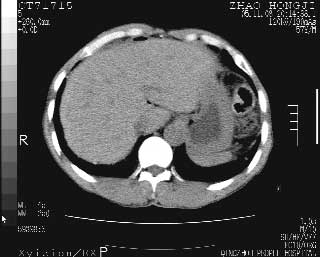

临床资料:男性,57岁,上腹部疼痛并5天,突然加重并延及全腹伴恶心5小时入院。胰淀粉酶化验在正常范围。检查:腹肌紧张,全腹压痛、反跳痛,尤以右上腹部为著。肠鸣音减低。血常规:wbc14.6x10/9, n:11.3x10/9 ,血压:135/90mmhg. 胸部透视:腹部肠腔轻度张气,未见其它异常改变。

胰腺形态规则,胰周脂肪间隙清晰,结合临床可排除急性胰腺炎

从图提示我同意空腔脏器穿孔的诊断,来源肠道{由于病程较短,故没能见到肠系膜聚局的征象}。

肝缘见少许气体,胰尾部见少许气体包饶(蓝色圈),12指肠上部或球部邻近胆囊周边也可见少许气体影(黄色圈),并忖托出胆囊壁,12指肠远段肠道内未见明显气体(白色箭)。

肝脏前缘见少量积气、胰尾部见少许气体包饶,肾前筋膜未见增厚,临床淀粉酶不高,意见:上消化道穿孔。

消化道穿孔。12指肠球部周和胰周积气考虑12指肠穿孔可能性大。

入院3小时后行剖腹探查术,见腹腔内大量脓性混浊液约1000ml,十二指肠球部溃疡穿孔,溃疡面约2.5x2cm,穿孔直径约0.6cm。胃内容物外益,周围组织炎性水肿明显。行十二指肠穿孔修补术。术后诊断:

1、十二指肠溃疡穿孔

2、弥漫性腹膜炎

对于少量的腹腔游离气体,ct检查较普通透视有绝对的优势,它不仅可以看到肝脏前上缘的气体,而且还能够看到小网膜区的游离气体。从而可以肯定诊断。各位分析战友的很好,感谢大家的参入!